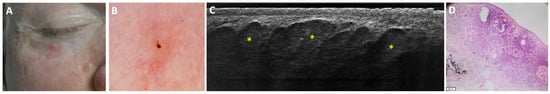

- Suppa, M.; Fontaine, M.; Dejonckheere, G.; Cinotti, E.; Yélamos, O.; Diet, G.; Tognetti, L.; Miyamoto, M.; Orte Cano, C.; Perez-Anker, J.; et al. Line-field confocal optical coherence tomography of basal cell carcinoma: A descriptive study. J. Eur. Acad. Dermatol. Venereol. 2021, 35, 1099–1110. [Google Scholar] [CrossRef]

- Ruini, C.; Schuh, S.; Gust, C.; Kendziora, B.; Frommherz, L.; French, L.E.; Hartmann, D.; Welzel, J.; Sattler, E. Line-field optical coherence tomography: In vivo diagnosis of basal cell carcinoma subtypes compared with histopathology. Clin. Exp. Dermatol. 2021, 46, 1471–1481. [Google Scholar] [CrossRef]

- Boussingault, L.; Lenoir, C.; Stefani, A.D.; Cappilli, S.; Fontaine, M.; Diet, G.; Miyamoto, M.; Cinotti, E.; Tognetti, L.; Pérez-Anker, J.; et al. Line-Field Confocal Optical Coherence Tomography of Basal Cell Carcinoma: Systematic Correlation with Histopathology. Diagnostics 2025, 15, 3059. [Google Scholar] [CrossRef] [PubMed]

- Donelli, C.; Suppa, M.; Tognetti, L.; Perrot, J.L.; Calabrese, L.; Pérez-Anker, J.; Malvehy, J.; Rubegni, P.; Cinotti, E. Line-Field Confocal Optical Coherence Tomography for the Diagnosis of Skin Carcinomas: Real-Life Data over Three Years. Curr. Oncol. 2023, 30, 8853–8864. [Google Scholar] [CrossRef]